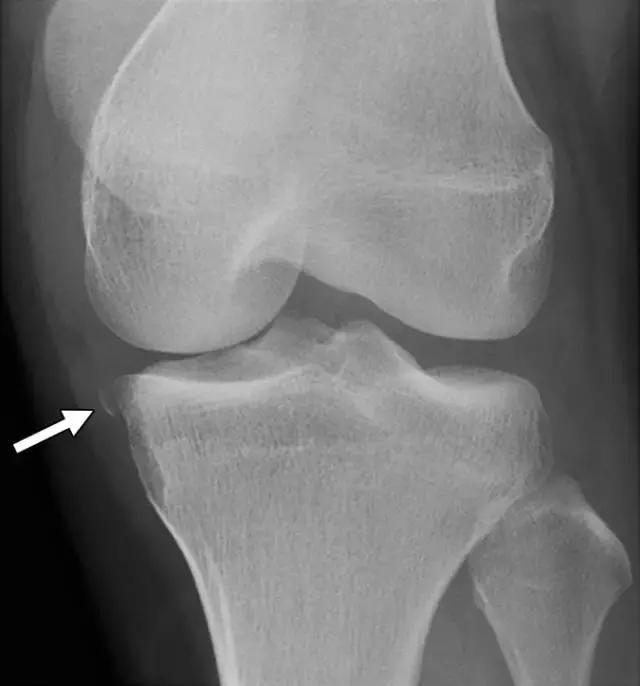

在放射照片上,Segond骨折显示为邻近近侧外侧胫骨平台的小骨片,并且在膝关节的前后放射照片上能很好的显示(图5A)。在MR图像上,由于相邻软组织中突出的异常信号强度,小的撕裂片段可能不像放射照片那样显着(图5B),但膝关节内更重要的损伤可以更好地显示。在75-100%的Segond骨折患者中发现ACL的撕裂,66-75%的病例中同时存在半月板损伤。

图5A -30岁的Segond骨折患者。A,膝关节前后位X线照片显示沿胫骨外侧平台的薄线状骨折片段(箭头)。